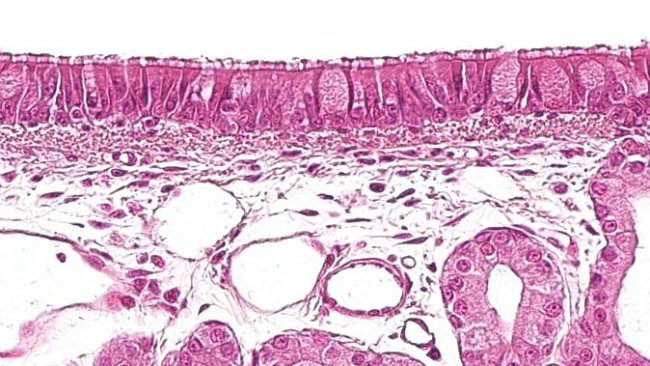

Die orale Impfung von Schweinen, die bisher auf enterische Krankheitserreger beschränkt war, entwickelt sich zunehmend zu einer innovativen Strategie gegen Atemwegserkrankungen. Durch die Nutzung des Potenzials des gemeinsamen mukosalen Immunsystems (Common Mucosal Immune System, CMIS) können neue Formulierungen ausgehend vom Darm Immunantworten in entfernten Schleimhautbereichen auslösen.